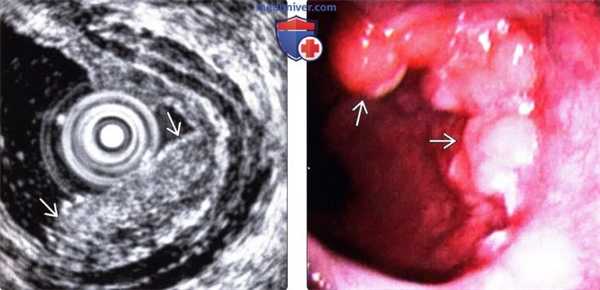

(Слева) На рентгенограмме определяется сужение просвета дистального сегмента пищевода в виде «огрызка яблока». Это переходная зона между проксимальной частью опухоли и неизменной частью пищевода. Слизистая оболочка в области опухоли разрушена, имеет узловатый вид.

(Справа) На рентгенограмме этого же пациента видны узло-видно утолщенные складки слизистой в области кардии, что позволяет предположить распространение опухоли на желудок. Кроме того, можно также предположить распространение рака желудка в дистальные отделы пищевода.

(Слева) При эндоскопической ультрасонографии выявлено внутрипросветное объемное образование, не проникающее через мышечную пластинку (аденокарцинома на стадии Т1а). Внутрипросветная сонография - лучший метод для определения глубины инвазии опухоли.

(Справа) На фотографии, полученной при эндоскопическом исследовании у этого же пациента, видно неправильной формы полиповидное объемное образование в дистальных отделах пищевода. Эта аденоарцинома была оперативно удалена путем эзофагэктомии с перемещением желудка в грудную полость.